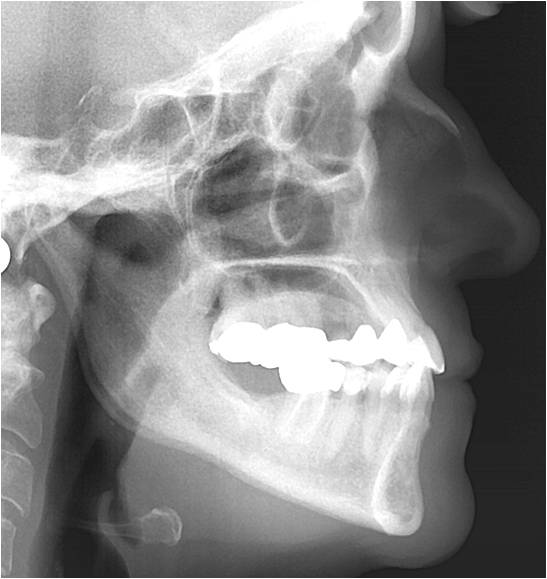

Behandlungsverlauf mit Fernröntgenseitenbilder

Im Fernröntgenseitenbild ist sichtbar, dass die Profilverbesserung der Patientin durch Retrusion der Unterkiefer Front erreicht wurde. Sehr interessant hierbei ist folgender Zusammenhang:

Vor Behandlung der Progenie

In Behandlung der Progenie

Jeder Mensch neigt dazu, sein Gesicht in der frontalen Ebene, achsengerecht d. h. im Lot, von Oben nach Unten, gerade zu stellen. So ist es typisch, dass Patienten mit einem Rückbiss das Kinn eher nach Vorne schieben und die Stirn eher nach hinten geneigt ist. Umgekehrt verhält sich der Patient mit Vorbiss (Progeniepatient) so, dass er den Kopf eher nach vorne unten neigt um wieder eine gerade Stellung des Gesichts zu erhalten. Diese unterschiedliche Neigung des Kopfes, hat einen erheblichen Einfluss auf die Atemwege! Der nach vorne geneigt Kopf verengt die Atemwege und der nach hinten geneigte Kopf öffnet die pharyngialen Atemwege. Durch die neue Kieferrelation, hat diese Patientin trotz Retrusion der Unterkiefer Front eine Verbesserung des respiratorischen Traktes mit Vergrößerung des Mesiopharynx erreicht.